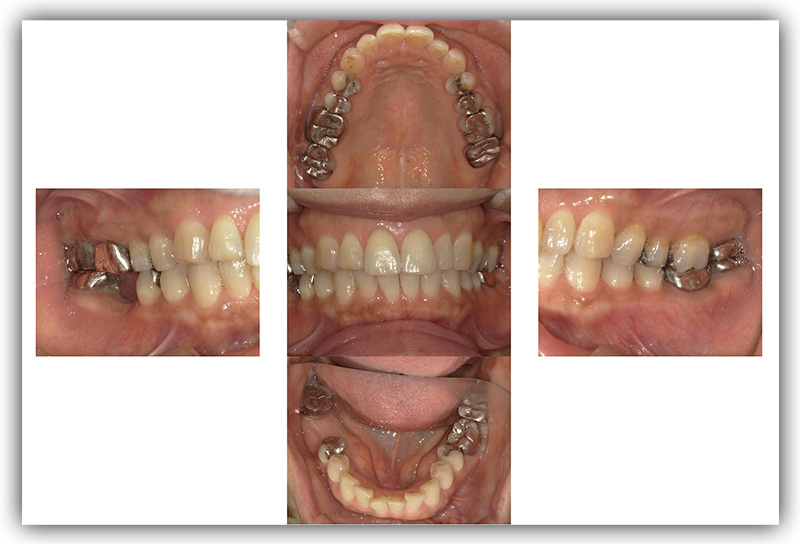

CASE_04

60代女性(インプラント)

- 患者さん情報(年齢・性別)

- 60代 女性

- 主訴

- 左下のインプラントを考えているが、怖い

- 治療箇所

- インプラント1箇所、セラミック3箇所

- 治療方法

- インプラント、セラミック治療

- 費用

- インプラント42.9万円、セラミック治療約24万円

- 治療期間

- 約1年6か月